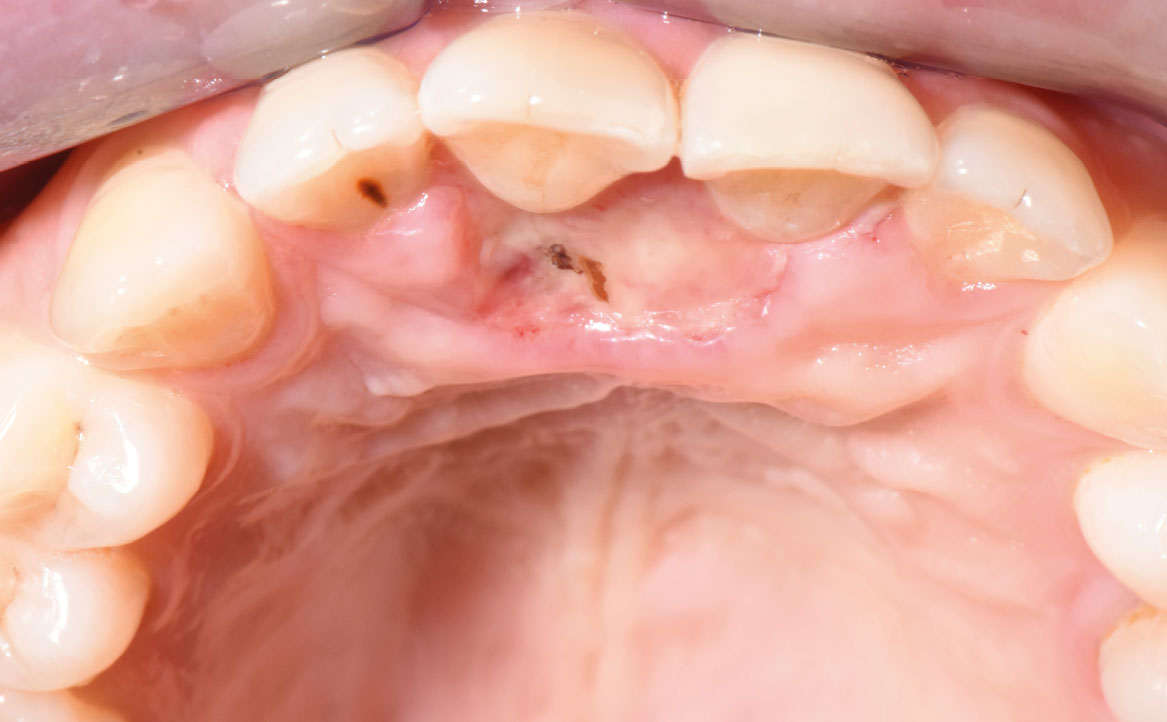

Il controllo clinico, avvenuto una settimana dopo l’escissione chirurgica della lesione, ha mostrato un aspetto roseo della mucosa e l’inizio della guarigione come visibile in figura 3.

In seguito, la paziente è stata sottoposta a controlli periodici fino alla completa guarigione della mucosa cheratinizzata.